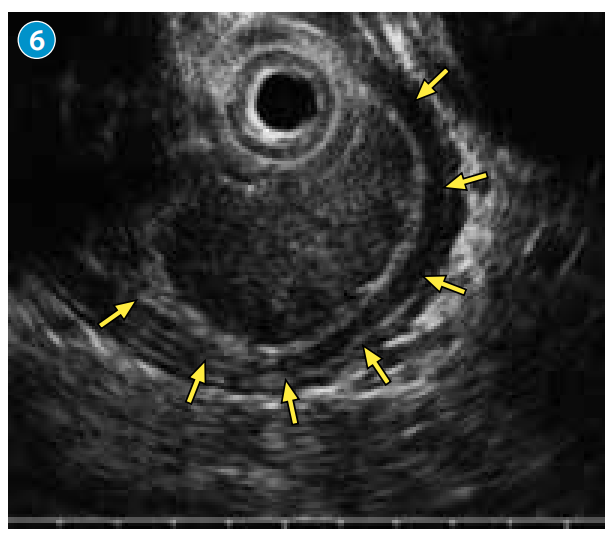

●探及以第2~3层为主体、整体具有厚度、呈低回声的隆起,病变向黏膜下层挤压性生长(→),无明显固有肌层浸润。

●综合判断病变为以上皮下发育为主体的黏膜下肿瘤。微细血管为不规则网状的R型血管。疑为特殊组织类型食管癌。